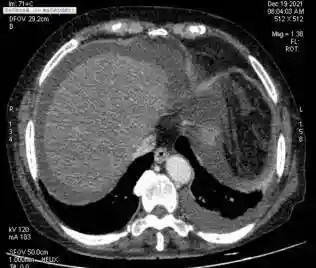

服用自种“三七”来养生,八旬老太吃出肝窦阻塞综合征